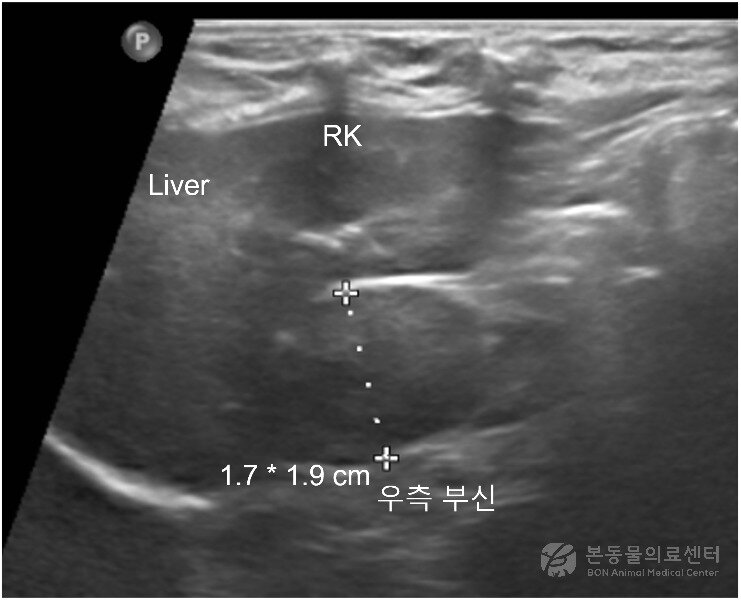

본문 이미지 - 10살 말티즈 복부 초음파 검사 결과 확인된 종양(본동물의료센터 제공) ⓒ 뉴스1

10살 말티즈 복부 초음파 검사 결과 확인된 종양(본동물의료센터 제공) ⓒ 뉴스1